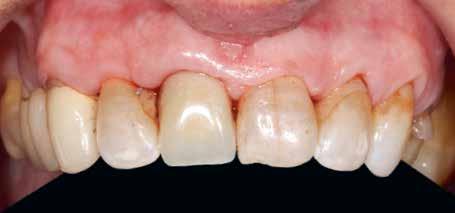

Esetismertetés

Az 50 éves nőpáciens az alsó és felső állcsont területén egyaránt panaszt (fájdalom, ráharapási érzékenység) okozó, harmadfokban mozgatható fogak miatt jelentkezett rendelőnkben. Az általános anamnézisben említést érdemlő betegség, műtét nem szerepelt. Az elvégzett klinikai és radiológiai vizsgálatok (1–2. ábra) alapján fogai reménytelen parodontális státusúnak bizonyultak, hosszú távon sem megtartásuk, sem protetikai célú felhasználásuk nem volt lehetséges. A parodontális prognózis a fogak eltávolításának abszolút indikációját jelentette. Ezáltal mindkét állcsontban teljes foghiány kialakulásával kellett számolnunk. A protetikai szemléletű, „visszafelé” tervezés elveit követtük a hosszú távú funkcionális, esztétikai siker és szöveti stabilitás elérése érdekében: mindkét állcsontban overdenture típusú fogpótlás készítése mellett döntöttünk. A megfelelő implant-protetikai rehabilitáció alapja az implantátumok megfelelő pozicionálása. A korábbi parodontális kórfolyamat következtében a processus alveolarisokat érintő eredendő csontdeficittel kellett számolnunk, amelyet tovább súlyosbíthatott volna a hagyományos extrakciós technikát követő involúciós atrófia. Ezért a páciens kivizsgálása és megfelelő előkészítése után a fog eltávolításával egy időben PRF

Sticky Tooth segítségével kivitelezett alveolus prezerváció mellett döntöttünk, a megfelelő csontos és mukogingivális gyógyulás minőségi és mennyiségi elősegítése érdekében. A PRF készítmény mennyiségét, minőségét, kezelhetőségét és hatékonyságát jelentősen befolyásolják a páciens laborértékei, ezért kezelési protokollunk szerint a műtétet megelőzően minden esetben laborvizsgálatot végzünk (hemoglobin: 134 g/liter, hematokrit: 0,43, fehérvérsejt: 6,6 G/liter, CRP: 13,60 mg/liter, vércukor: 6,2 mmol/liter, összkoleszterin: 7,00 mmol/liter, triglicerid: 1,08 mmol/liter, HDL koleszterin 2,57 mmol/liter, LDL koleszterin 1,12 mmol/liter), D3 vitamin: 117,5 nmol/liter).

A fogak eltávolítása és az alveoláris csont megőrzésének és regenerációjának segítése céljából elvégzett augmentáció altatásban történt. Óvatos, atraumatikus extrakciót követően eltávolítottuk a parodontális és periapikális gyulladásos folyamatok eredményeként jelen lévő sarjszövetet. A bukkális csontfal hiánya és a tervezett vertikális augmentáció miatt indokolt membrántechnika megfelelő kivitelezése céljából a felső állcsonton mukoperioszteális lebenyt képeztünk (3–4. ábra). Az alveolus prezervációt Sticky Tooth, PRF és titánerősítésű teflon (PTFE-Ti) membránok segítségével végeztük el, a J. Choukroun által megadott vérvételi és centrifugálási protokoll (28) elveinek betartásával: kizárólag Process for PRF Duo Quattro System eszközöket, centrifugát, vérvételi egységet és csöveket, a membránok előállításához PRF Boxot használtunk. Az A-PRF és S-PRF csöveket a PomPac eljárásnak megfelelően 4 Celsius-fokra előhűtöttük. Az eltávolított fogak makroszkópos tisztítását és darabolását nagy fordulattal (300 000 RPM) fogászati turbinába helyezett gyémántfúróval végeztük, majd Tooth Transformer™ berendezéssel, annak gyári reagens rendszerével kezelt őrleményt nyertünk. A Sticky Tooth készítmény előállítása a PRF készítmény és az őrlemény